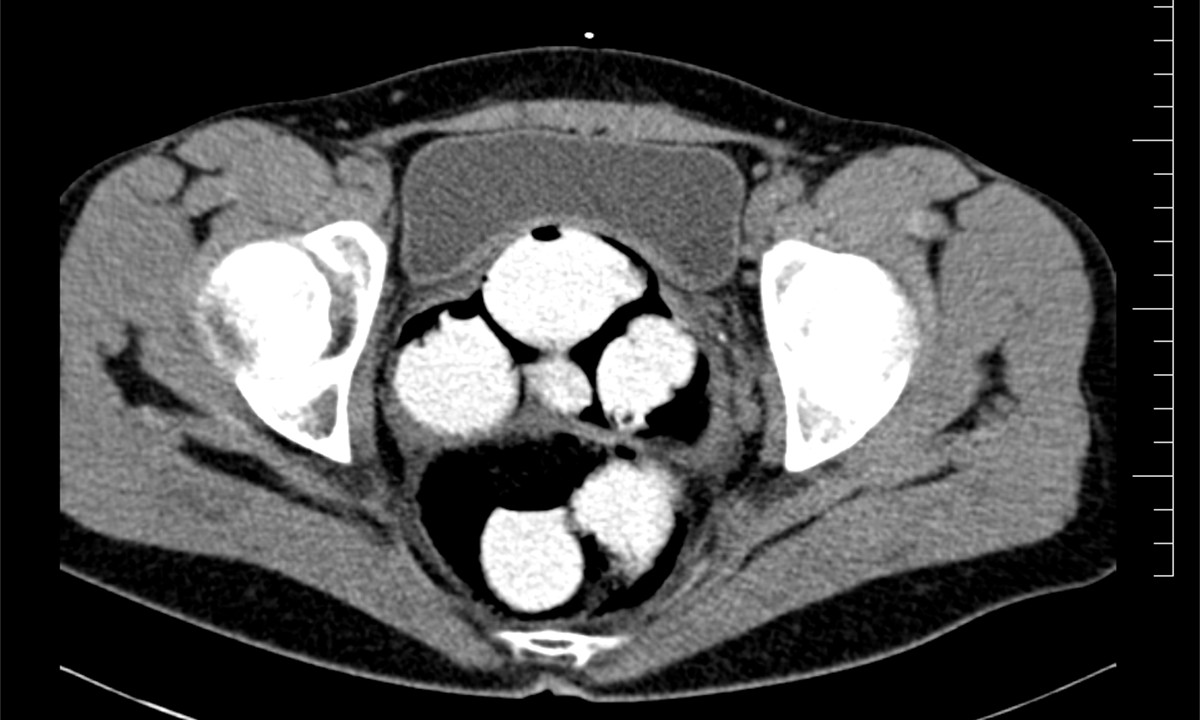

Ke kontrole byl polykač celníky vytipován na základě provedené rizikové analýzy daného letu. Prvotní podezření na pašování drog celníkům potvrdily kontrolní stěry z rukou pašeráka.  Při důkladné kontrole jeho zavazadel a osobní prohlídce nebyly drogy nalezeny, proto bylo provedeno následné CT vyšetření, které podezření potvrdilo.

Postupně z těla pašeráka vyšlo 112 kontejnerků naplněných bílým práškem. Chemická látka při provedení detekční zkoušky pozitivně reagovala jako kokain. Celková hmotnost všech kapslí je více než 1,2 kg. Určení vlastní hmotnosti a druhu zajištěné drogy je předmětem další odborné expertízy. Podle zkušeností celníků se s největší pravděpodobností jedná o velmi koncentrovaný kokain. Zda byla droga určena na český trh nebo k distribuci v jiné zemi, je předmětem dalšího šetření.